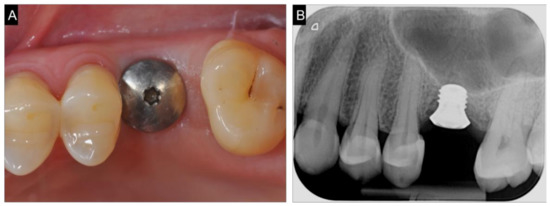

2.1. Planning

2.2. Surgical and Prosthetic Procedure